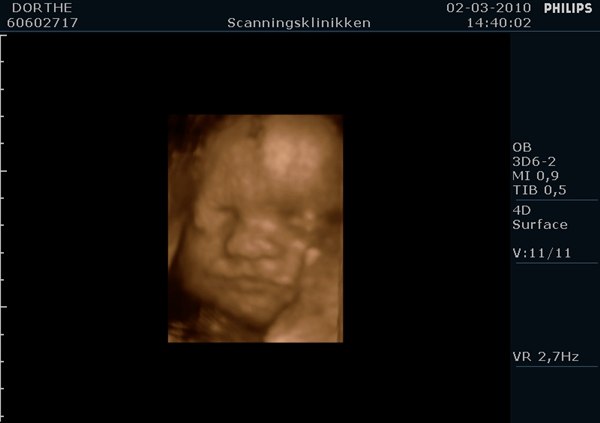

Lige siden jeg fik 3D scannet min baby i maven har jeg været spændt på om nu den lille fis så også lignede billedet fra maven når hun kom ud.

Jeg ved ikke med jer, men jeg er sgu´ imponeret over ligheden